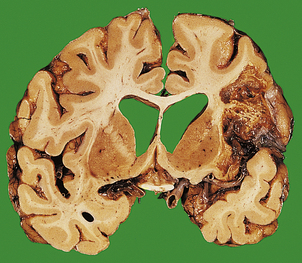

Acquired hydrocephalus can result from any lesion that obstructs the CSF pathway (Fig. 26.8). Expanding lesions in the posterior fossa are particularly prone to cause hydrocephalus, as the fourth ventricle and aqueduct are easily obstructed. Some lesions may cause intermittent obstruction, particularly colloid cysts of the third ventricle which may block the foramen of Monro. Obstructive hydrocephalus commonly results from the organisation of blood clot or inflammatory exudate in the CSF pathway following an episode of haemorrhage or meningitis (Fig. 26.9). Intermittent pressure hydrocephalus is thought to result from defective CSF absorption at the arachnoid villi.

image

Fig. 26.9 Longstanding hydrocephalus. image The lateral ventricles are very dilated and contain a prominent choroid plexus (arrow). The overlying white and grey matter are atrophic. Fibrous adhesions are present in the ventricles posteriorly, suggestive of previous infection. image In the same case, the cerebral aqueduct in the midbrain is completely obliterated by glial tissue as a consequence of a previous viral infection (arrow). This has resulted in obstructive hydrocephalus.